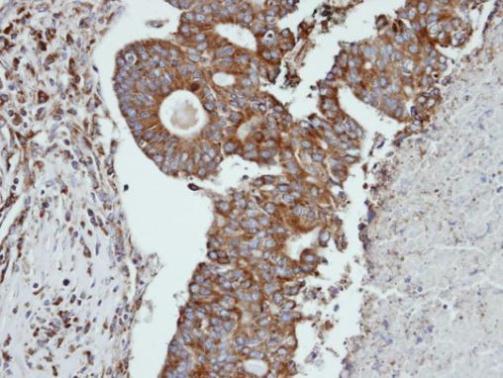

Immunohistochemical analysis of paraffin-embedded human endo mitral ovarian cancer, using CTSS(GTX103988) antibody at 1:100 dilution.

Antigen Retrieval: Trilogy™ (EDTA based, pH 8.0) buffer, 15min